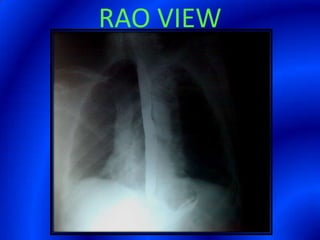

This document provides information about a barium swallow procedure. It begins with an introduction and overview of the embryology and anatomy of the pharynx and esophagus. It then describes the procedure itself, including preparation, technique, views obtained, and indications. Specific conditions that may be examined include pharyngeal and esophageal webs, foreign body impaction, scleroderma, dysphagia, mediastinal masses, and carcinoma. Diagrams are provided to illustrate normal anatomy and various pathological findings.